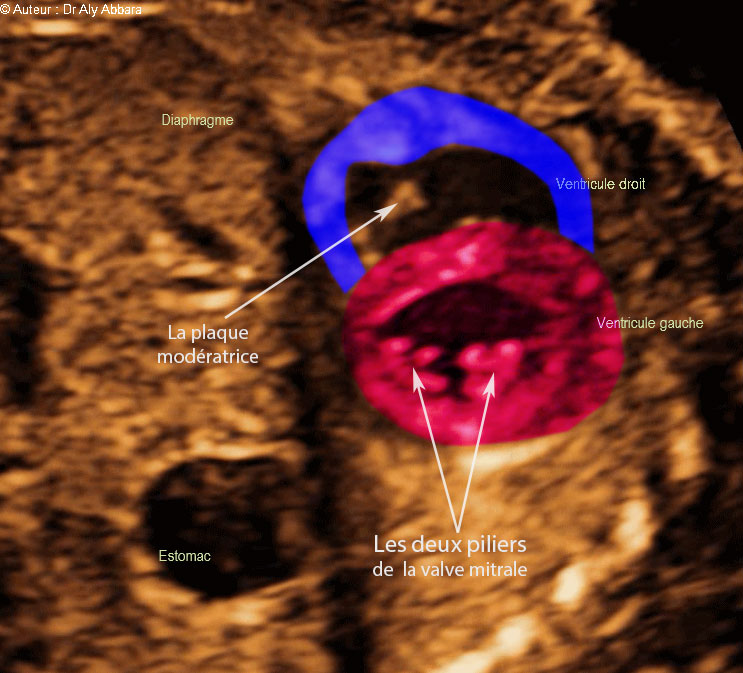

Images échographiques montrant l'aspect normal de la coupe cardiaque passant par la pointe du cœur et qui comporte de haut en bas sur cette image :

* La partie fundique du ventricule droit contenant la plaque modératrice de la valve tricuspide.

* Le septum interventriculaire qui en continuité avec les parois du ventricule gauche.

*La partie fundique du ventricule gauche contenant les deux piliers de la valve mitrale.

On peut identifier également sur cette image le diaphragme séparant l'estomac de la cavité de la cage thoracique.

Foetus de 22 SA et 3 jours.